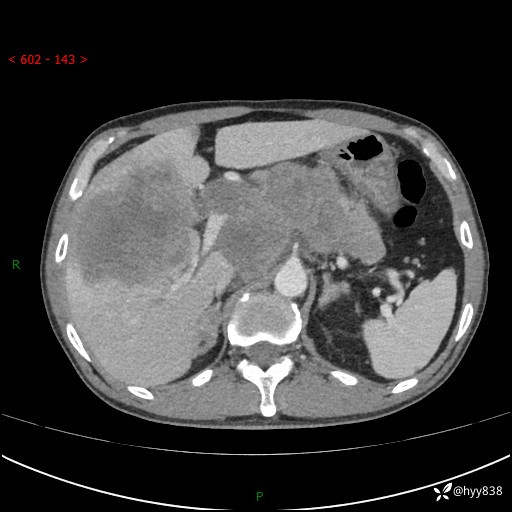

上腹部CT平扫+增强(两期)